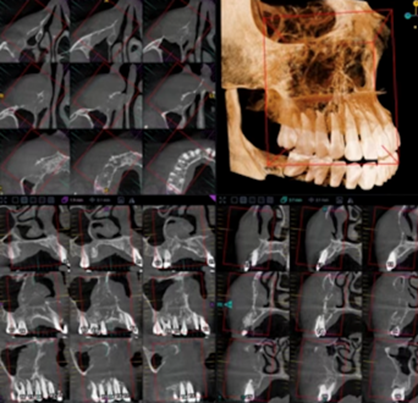

In case of a possible malignant neoplasm, the patient was referred for cone beam computed tomography of the maxilla and maxillary sinus (Figure 4). An ill-defined region of bone loss was located within the right maxilla, extending from site 1.6 to site 1.1 and from the crestal aspect of the alveolar process superiorly to involve the anterolateral wall of the right maxillary sinus, the right lateral nasal wall, as well as the right infraorbital canal. Radiographic findings further indicated a prominent, irregularly shaped widening of the periodontal ligament spaces around the roots of teeth 1.6, 1.5, 1.4, 1.3 and 1.2, and the interradicular bone between these teeth exhibited ill-defined osteolysis intermixed with irregularly shaped strands of sclerotic bone. Multiple ill-defined discontinuities were observed along the buccal cortex of the alveolar process overlying these areas, as well as the contiguous anterolateral wall of the maxillary sinus and lateral wall of the nasal fossa. Linear, spiculated strands of bone formation were evident emanating from the anterolateral surface of the right maxilla in a perpendicular orientation to the cortex. A large, dome-shaped soft tissue mass was evident extending from this cortical dehiscence extending anteriorly to the facial fat planes, into the interior nasal meatus anteriorly, and into the right antral space and infraorbital canal in the posterior direction.

Figure 4: Cone beam computed tomography showing an ill-defined osteolytic lesion in the right maxilla with cortical perforation and soft tissue extension, suggestive of malignancy.

More specifically, these observations indicated a mass on the posterior-superior aspect that extended into the right infraorbital canal (Figure 5). Discontinuities were observed along the medial inferior walls of the anterior aspects of the canal. Moreover, the superior wall of the canal appeared elevated and thinned but not fully discernible radiographically. The overall diameter of the right infraorbital canal appeared abnormally enlarged, indicating possibility of perineural spread. These radiographic findings were suggestive of malignancy involving the right maxilla. Medical referral was indicated for further evaluation and management.

Figure 5: Cone beam computed tomography demonstrating suspected extension of the lesion into the right infraorbital canal.

The radiographic presentation necessitated consideration of several malignant processes in the differential diagnosis. Osteosarcoma was initially contemplated due to its potential for aggressive maxillofacial bone destruction; however, typical radiographic characteristics, such as mixed radiopaque-radiolucent appearances, osteoid matrix deposition, and prominent sunburst periosteal reactions were absent. Instead, the lesion demonstrated diffuse periodontal ligament widening, permeative osteolysis, cortical perforation, and extensive soft tissue extension, features more consistent with lymphoproliferative malignancies. The lack of mineralized matrix production further diminished the likelihood of osteosarcoma. Moreover, the unexplained enlargement of the infraorbital canal suggested possible perineural involvement, a finding that can accompany aggressive lymphomas. Collectively, the radiographic and clinical characteristics favored a diagnosis of a high-grade B-cell lymphoma, prompting an incisional biopsy to obtain definitive histopathological confirmation.